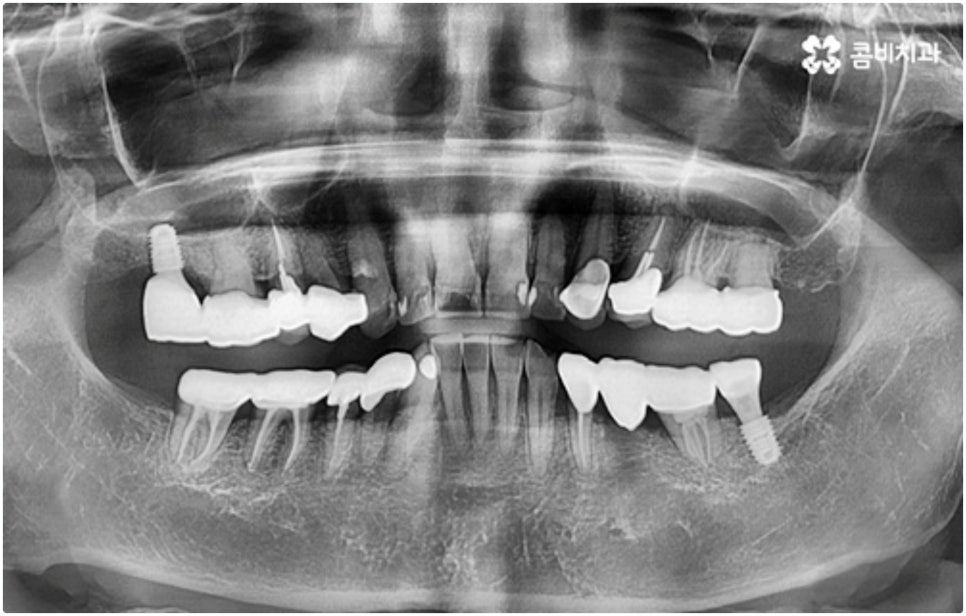

어금니는 저작력이 많이 걸리는 치아이기 때문에 보철물 제작에 있어서도 강한 자극에 잘 견딜 수 있는 튼튼한 재질을 고르는 것이 중요한데 요즘은 이러한 내구성과 함께 심미적인 부분도 함께 고려하는 추세라서 어금니임플란트 시술시 지르코니아 크라운을 선택하시는 분들이 많이 있습니다.

또한 자체 기공소를 갖추고 있는 치과라면 의료진과의 긴밀한 협조를 통해 보다 빠른 시간 내에 좀 더 잘 적응할 수 있는 맞춤 보철물 제작이 가능할 것이기 때문에 환자분들의 불편을 덜어주는 데 도움을 주는 이런 사항들 역시 꼼꼼하게 체크해 보시길 권유드리고 있어요.